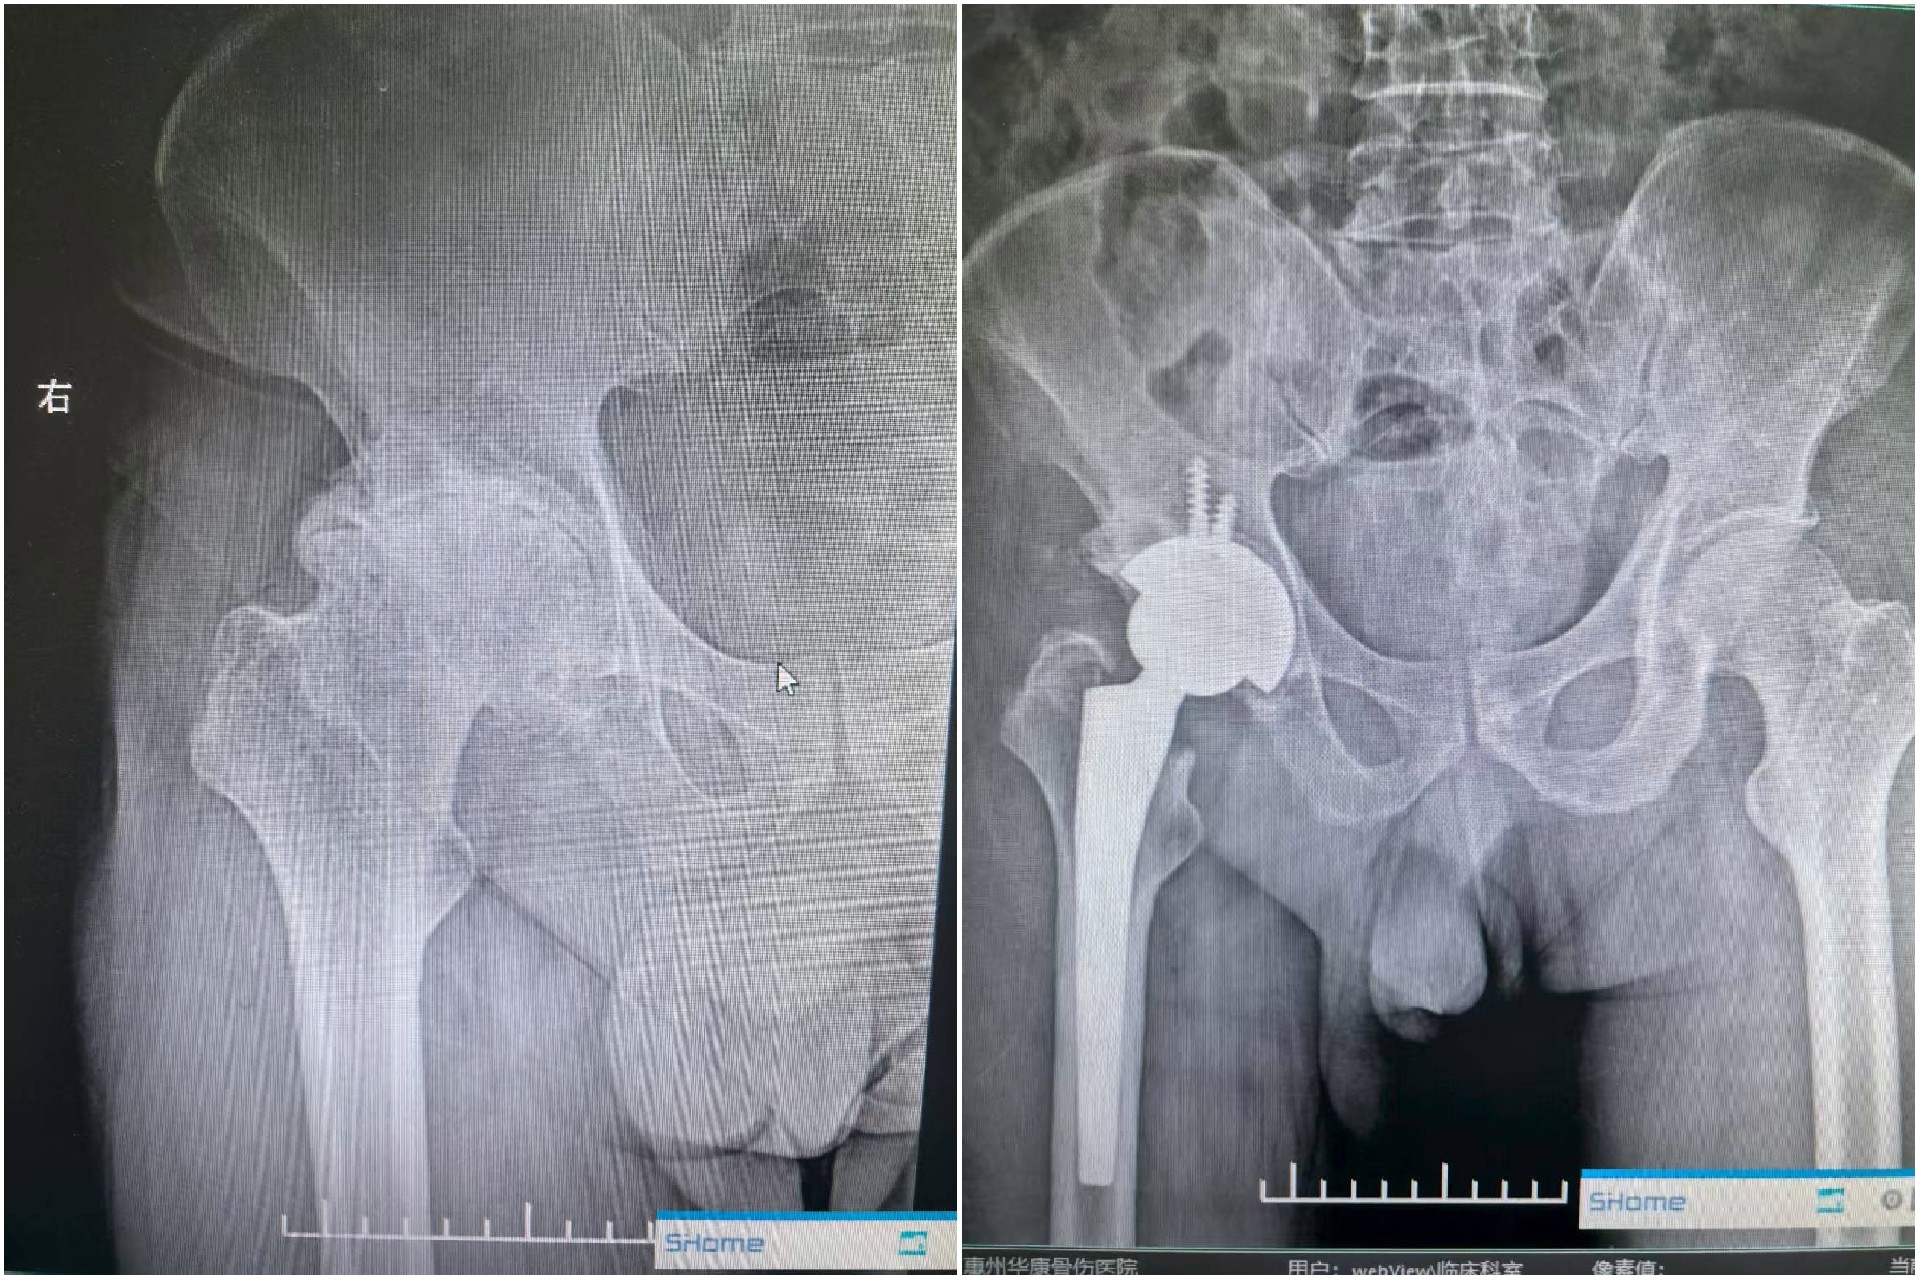

微信图片_20250725153404.jpg

术前与术后影像

骨科伍见锋主任细询问了他的情况并通过检查发现,患者股骨头已经明显的变形,呈现出塌陷变扁的状态,髋臼边缘的骨质也出现了硬化现象,髋关节间隙显著变窄,患者长期饮酒,久而久之,患上了严重骨质疏松,以及“酒精性股骨头坏死”。

在排除了保守治疗的可能性后,伍见锋主任团队为他制定了个性化的人工全髋关节置换手术治疗方案。经过周密的术前准备和精细的手术操作,手术顺利完成。次日,患者即独立下地行走,疼痛症状已基本消失。术后患者表示,有种“历经百般折磨,终于重获新生”的感觉。